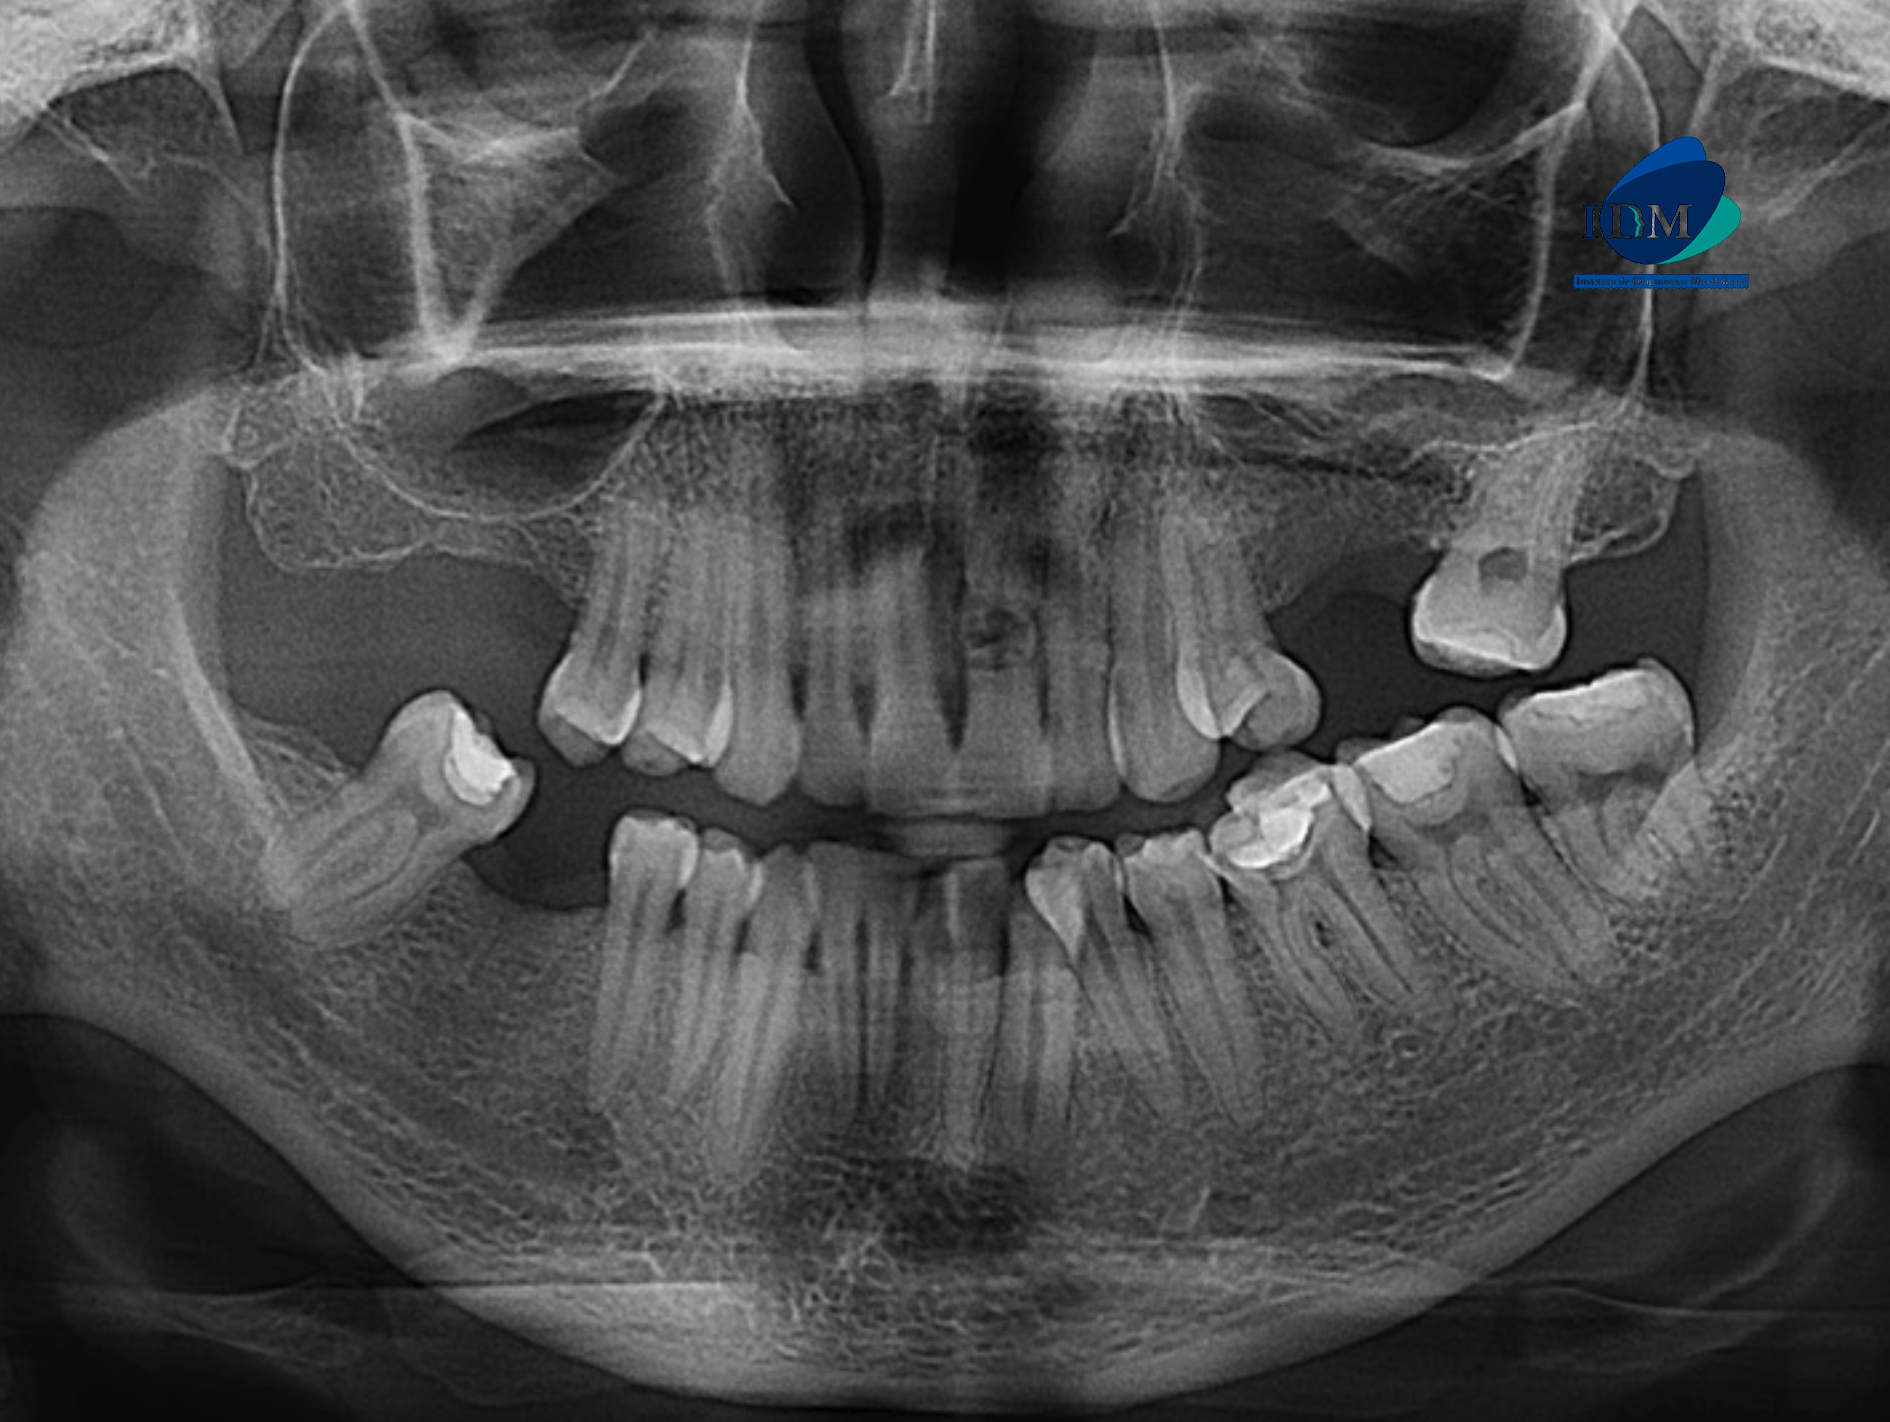

Paciente femenino de 43 años de edad, es referido al Instituto de Diagnóstico Maxilofacial – IDM para evaluación general.

En la radiografía panorámica (Figura 1), se aprecia piezas dentarias con material de obturación, además se evidencia imagen radiopaca definida a nivel apical de pieza 21.

Radiografia Panorámica